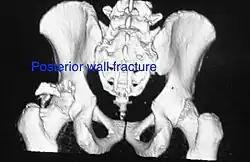

Posterior wall This is the most common variety of acetabular fracture. It typically occurs due to dashboard injury; when a person travelling in a vehicle involved in a head-on collision, the force applied over the flexed knee travels along the femur bone to the head of the femur, breaking the posterior wall of the acetabulum. The head of the femur is dislocated outside the joint. T shape When a transverse fracture also had a vertical fracture line, it is called a T shape fracture. Here the innominate bone is broken in such a way that all three parts of it, the ilium, the ischium and the pubis are separated from one another. This is a three part fracture. Though both columns are broken, the weight bearing dome is still attached to the main part of the ilium and hence it is not a true fracture of both columns.

Posterior column As with posterior wall injury, this also typically occurs due to dash board injury. Posterior column + Posterior wall These fractures are extensions of elementary fractures. With the involvement of the posterior wall, the difficulty in treatment increases. These fractures are rarely amenable to non-surgical treatment. Due to posterior wall fracture, the hip is usually dislocated posteriorly, requiring immediate reduction of dislocation and surgical reconstruction after a few days.

• Posterior wall fracture: Iliac oblique and obturator oblique views

• Posterior column fracture: Iliac oblique and obturator oblique views